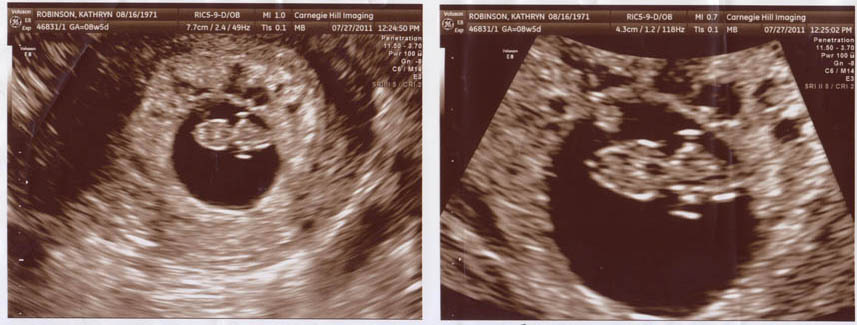

11 Weeks

9 Weeks